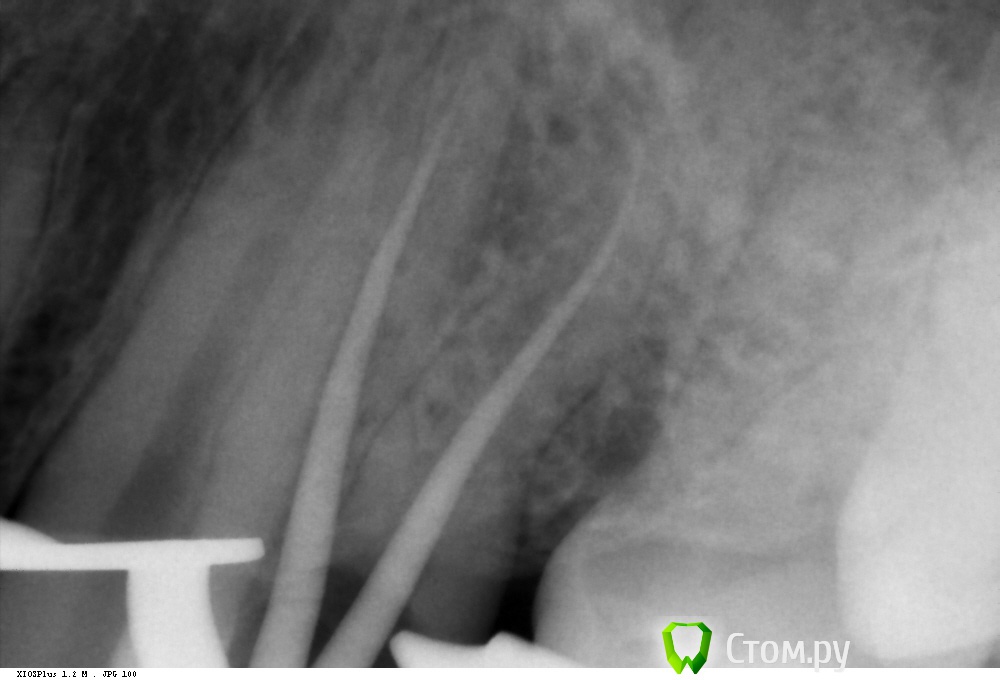

Shaid Опубликовано 9 февраля, 2014 Автор Поделиться Опубликовано 9 февраля, 2014 Первый сломанный Протейпер.Ds: хронический пульпит 46. После ковровой 25 ломанул S1 в мезиально-щечном. Обошел ручными кое-как) Отломок заклинил на стенке канала. Подцепляю H-файлом, не идет. Ультразвуком тоже пытался.Коллеги, если попробовать клеем и он заклеит обходной путь к апексу, его можно будет потом пройти файлами?Посоветуйте! Ссылка на комментарий

Kolchanov Опубликовано 9 февраля, 2014 Поделиться Опубликовано 9 февраля, 2014 Оставь его в покое, раз обходится. Он в перешейке, пусть там и остается. Будешь долбить, потом он в апекс упадет и вообще фиг достанешь. А в дистальном что раскорячилось? Ссылка на комментарий

Shaid Опубликовано 9 февраля, 2014 Автор Поделиться Опубликовано 9 февраля, 2014 А в дистальном что раскорячилось? Хах! Знал, что кто-нибудь спросит Самому интересно) После снимка посмотрел дистальные - все норм) Ссылка на комментарий